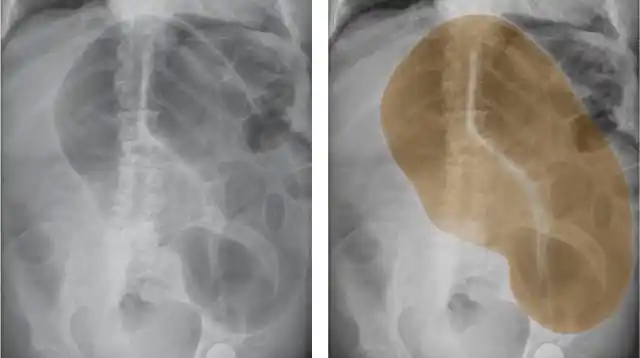

怎么样?再看几例试一试:右图 棕色 区域示乙状结肠扭转.